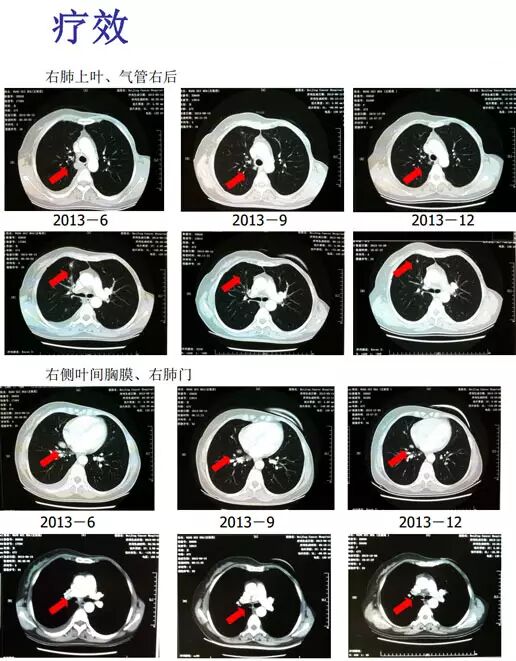

总结:①诊断一元论:有乳腺癌病史的患者出现恶性肺部病变,不能仅考虑为肺癌,乳腺癌合并其他肿瘤的可能性很小(<10%),乳腺癌肺转移的可能性更大;②内分泌治疗的重要性和有效性。

宋国红教授:这位患者无疾病生存期很长,10 年后出现乳腺癌复发转移,转移病灶是肺内小结节、胸水,疾病进展不快,非常符合内分泌治疗适应证。患者处于绝经前,既往只采用过他莫昔芬治疗,因此首先进行卵巢抑制治疗,药物去势相对安全有效。患者他莫昔芬治疗结束5 年之久,再次他莫昔芬治疗可能有效,但是为了使治疗更有把握,我们选择了AI治疗。